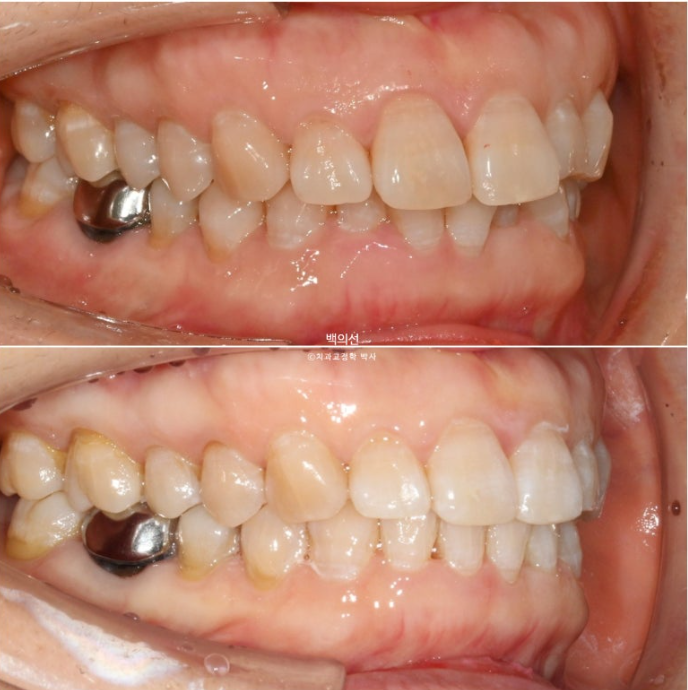

24.10~25.07

빈공간으로 내려와있던 큰어금니를 함입시켜 비로소 임플란트 심을 공간이 확보되었습니다.

바로 뒤에 발치시기를 미루고 치료에 이용된 제 2대구치는 임플란트 수술과 함께 발치할 예정입니다.

가지런해진 아래 앞니

정돈 된 스마일라인이 돋보이네요

앞니돌출은 개선되었습니다.